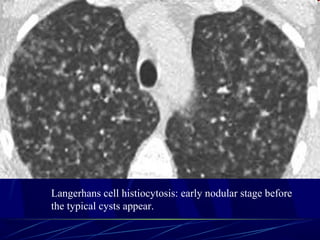

๏ฌ Langerhans cell histiocytosis

(early nodular stage)

Langerhans cell histiocytosis: early nodular stage before

the typical cysts appear.